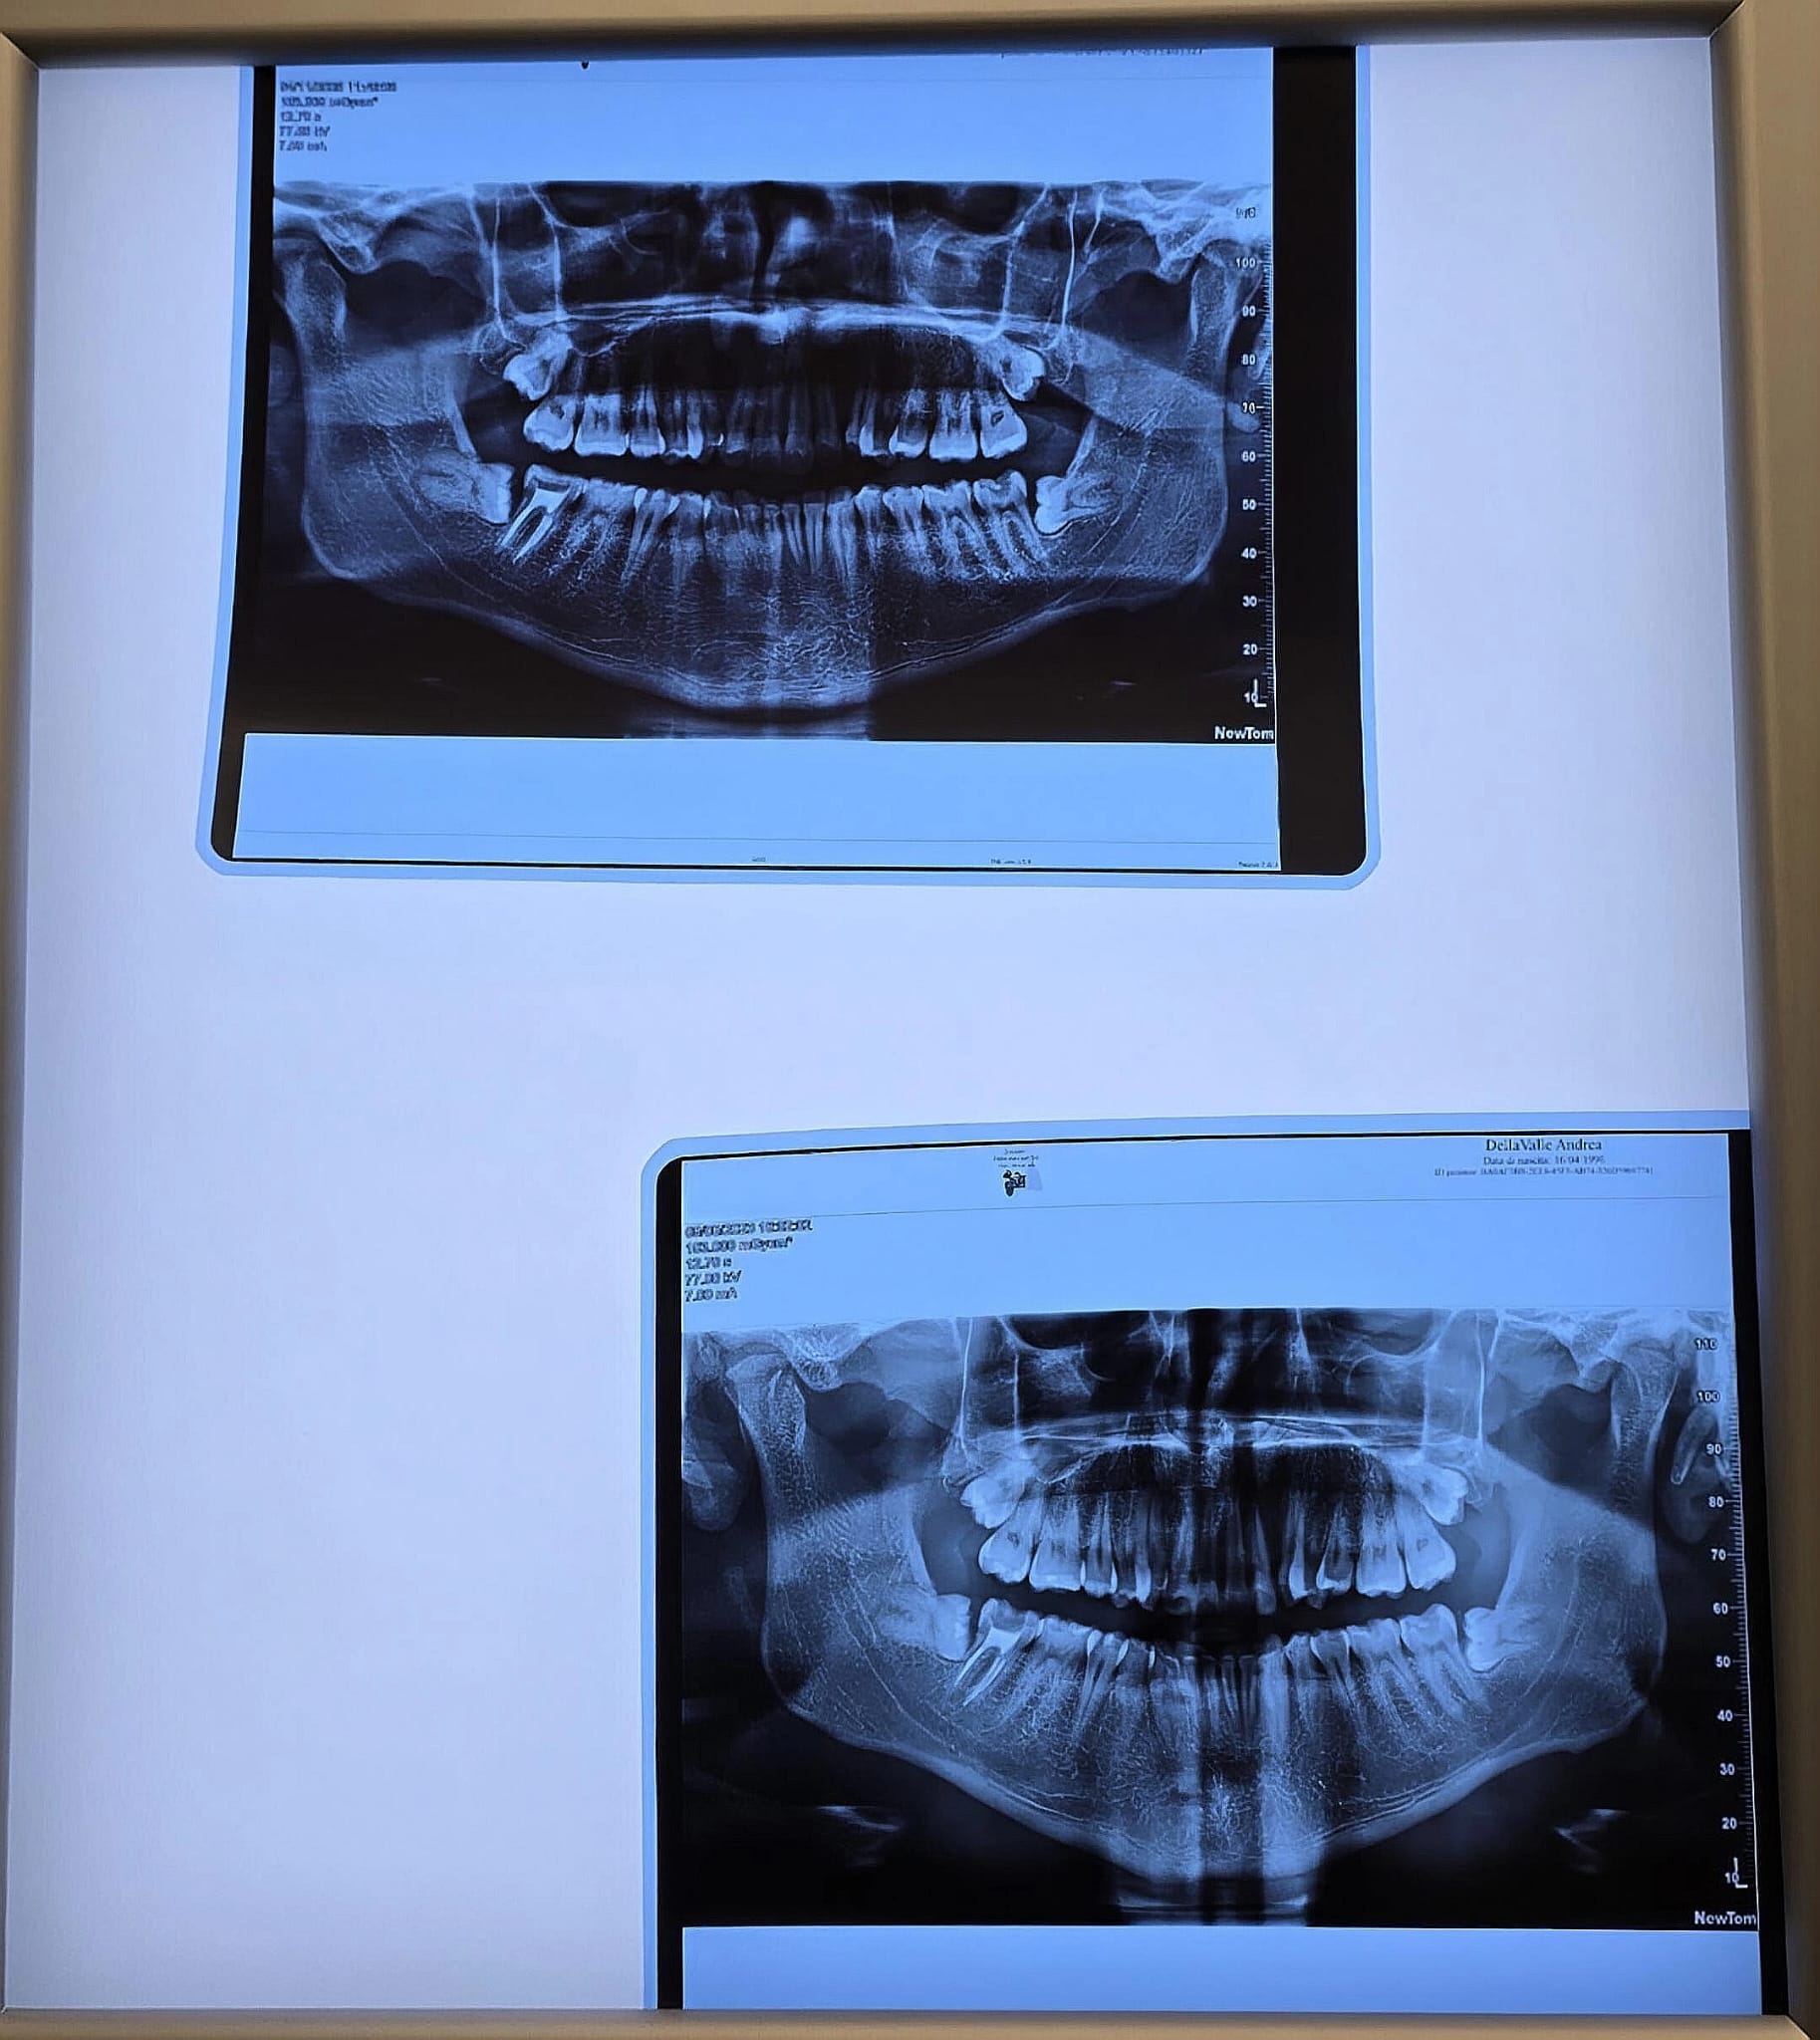

Buongiorno Lunedi 19 gennaio mi sono sottoposto all'estrazione di due denti del giudizio di un lato Inferiore e superiore) e due mesi prima gli altri due denti lato opposto. Purtroppo durante l'estrazione del giudizio superiore il medico ha rotto la radice che è rimasta all'interno del sito e non si è sentito di rimuoverla per non creare danni al sinus mascellare. Così viene chiusa la ferita e mi viene detto che in taluni casi è una pratica consolidata e studiata nella medicina e che non porterà a conseguenze poichè essa verrà inglobata dal nuovo osso e dimenticata nel tempo. Io mi sono informato tanto a riguardo e vi è una forte contrapposizione di idee in materia. Ha voluto subito eseguire una tac a fine operazione per vedere il residuo radicolare come fosse posizionato e ha confermato la scelta di non aver voluto intervenire per la rischiosità. Adesso posso capire il rischio, ma sarebbe certamente stato da valutare prima di iniziare il tutto (ovviamente avevamo la tac della situazione con tutti i denti), soprattutto perchè i denti fossero inclusi e sani. Eventualmente rimandare a un altro esperto il lavoro. Avrò una visita di controllo il 27 Gennaio e la rimozione dei punti la settimana successiva. Detto ciò, ormai è andata così e adesso in fase di recupero mi sto informando per avere dei pareri riguardo la situazione attuale e se fosse necessario un altro intervento per l'estrazione della radice o se farmene definitivamente una ragione e sperare che nella vita non si presentino mai delle complicanze. Inoltre ho eseguito queste estrazioni in previsione di applicare l'ortodonzia invisibile. Ho recuperato la CBCT e vorrei allegare qualche immagine che ho estrapolato per darvi un idea. Mi sto informando ovunque e tanti sul web mi hanno riferito che purtroppo a danno fatto (quasi certamente dovuto all'inesperienza del medico) a volte le radici si lasciano nel sito e che con alta probabilità potrebbero non dare problemi per tutta la vita. Io non sono tranquillo purtroppo perchè avrei tanto voluto chiudere questa parentesi (i denti superiori inclusi erano sani e privi di dolore) e ora mi ritrovo ad avere il pensiero che un domani potrei avere problemi. Vi chiedo cortesemente il vostro parere riguardo questi eventi e se avete mai consigliato di rimuoverle successivamente. Inoltre il mio timore è che fra qualche anno l'osso riformato renda molto più complicato l'intervento di rimozione rispetto a un alveolo occupato da un dente da estrarre. Grazie per la disponibilità.

Nessuna delle immagini inviate può mostrare il vero rapporto fra la radice ed il seno.. Bisogna vedere tutte le immagini complete della cone beam.. Non sono del tutto d'accordo con la sua valutazione di inesperienza del dr che ha fatto l'estrazione. Questo non va in contrasto con quello che le ho detto già nella precedente risposta, cioè che esiste chi la può rimuovere senza danni. E le valutazioni pre-estrazione cui lei da la colpa, mai possono essere veramente perfette, Può capitare a chiunque.. ma lei aveva fatto una CBCT anche prima??? Non pensi troppo a quello che è successo, ma pensi a cosa deve fare ora.